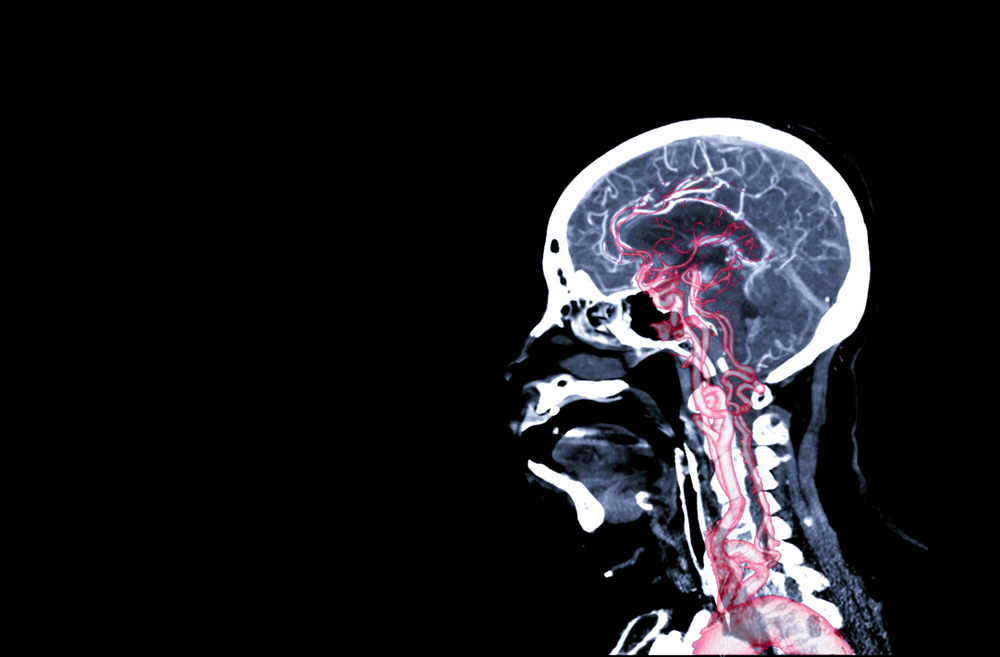

Iš anksto pastebėti pokyčius aortos lanko srityje yra sudėtinga, nes simptomai dažniausiai išryškėja tik tada, kai kraujagyslės jau labiau susiaurėjusios. Diagnozei gydytojai taiko įvairius ištyrimo metodus.

Vienas jų – širdies magnetinis rezonansas. Šis tyrimas leidžia išgauti detalius širdies ir pagrindinių arterijų vaizdus naudojant galingus magnetinius laukus. Kita vertus, echokardiografijos metu taikomi garso bangų impulsai, kurie realiu laiku parodo širdies struktūras ir funkcijas.